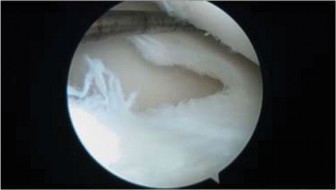

The correct answer is (C). The arthroscopic images demonstrate a complete discoid meniscus which is covering the entire lateral tibial plateau. As the patient is symptomatic from the meniscus, saucerization is the first step in management. The meniscus is trimmed back using a combination of shavers and biters to a stable peripheral rim, which replicates the width of the native meniscus. Complete meniscectomy would not be indicated in a patient of this age due to the high risk of early onset degenerative arthritis. In fact, even prior to intervention, many discoid menisci have been associated with the development of lateral hemijoint osteochondral lesions. Although chondroplasty may be necessary, the meniscus is the underlying problem causing chondral wear and must be dealt with first. After saucerization is performed, the meniscus is probed and the following arthroscopic image is seen (Fig. 10–33). The next step in management is:

Figure 10–33

Discussion

The correct answer is (D). The arthroscopic image demonstrates an unstable peripheral rim of the meniscus which an attempt should be made to repair. The meniscus has been trimmed adequately but instability remains. Further saucerization without repair may lead to very little to no meniscus remaining which can lead to early degeneration. Although chondral damage may be present in association with the meniscus, there is no exposed subchondral bone to suggest the need for microfracture. Various repair techniques (inside-out, outside-in, all-inside) are available to the surgeon and should be utilized based on surgeon preference and experience. Objectives: Did you learn...?